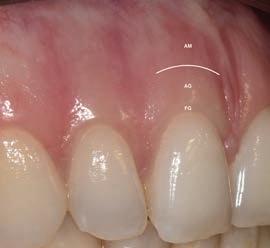

The main role of the periodontium is to anchor a tooth to the jaw bone. The periodontium consists of the gingiva, periodontal ligament, root cementum and alveolar bone proper.1 The periodontium also plays a major role in defence which contributes to its health in the natural dentition as well as around dental implants.1, 2 Three types of oral mucosa can be distinguished, namely the masticatory mucosa (gingiva and hard palate), specialized mucosa (dorsum of the tongue) and lining/alveolar mucosa. The gingiva covers the coronal alveolar process and cervical portion of teeth and consists of an epithelial layer and underlying connective tissue. The gingiva is always keratinized and consists of the attached gingiva and the free gingiva which terminates at the free gingival margin. Apically, the attached gingiva extends to the mucogingival junction, where it becomes continuous with the alveolar mucosa (Fig.1). The immobile attached gingiva is firmly attached to the underlying alveolar bone and cementum by connective tissue fibers (Sharpey’s fibers). The alveolar mucosa on the other hand, is loosely bound to the underlying lamina propria and is therefore mobile.1

The width of the band of attached gingiva around teeth varies from site to site and the range of variation is between 1-9 mm. In the maxilla, the vestibular gingiva is usually widest at the incisors and narrowest at the premolars. In the mandible, the lingual gingiva is especially narrow at the incisors and wide at the molar sites (Fig. 2).1 This explains why certain potential dental implant sites will naturally present with less attached gingiva after tooth extraction.

Figure 1: Healthy soft tissue in the natural dentition. FG= free gingiva, AG=attached gingiva, AM=alveolar mucosa

Figure 2: Variation in the width of attached gingiva at different sites, with a clearly visible mucogingival junction.